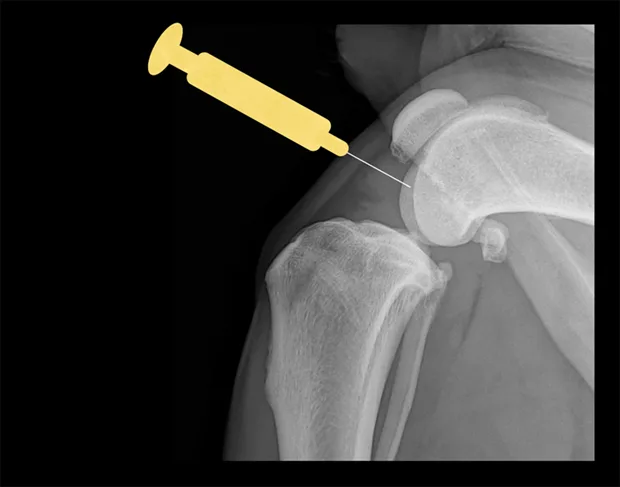

Shoulder

Place the patient in lateral recumbency with the shoulder joint in a neutral position. For large dogs, insert the needle about 0.5–1 cm distal to the acromion process of the scapula in a lateral-to-medial direction; a lateral radiograph of the shoulder joint may help determine the distance from the distal acromion to the joint space. The needle may need to be passed in a slightly dorsal direction to enter the joint. A 1.5-inch needle is adequate for even large-breed dogs.

Craniocaudal view of shoulder. Place needle just distal to the acromion (yellow dot), angled slightly dorsally.

Lateral view of shoulder. Insert needle just distal to the acromion (yellow dot).